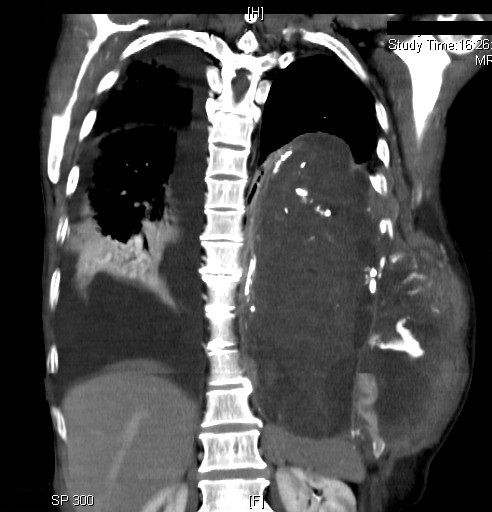

Gastrointestinal Complication of Granulomatosis with Polyangiitis - CTA was highly suggestive of bowel ischemia with wall thickening of the distal duodenum and jejunal loops (white arrow) with adjacent fat stranding and mesenteric edema (orange arrow) and free fluid in the

Typical involvement includes the ear, nose, and throat, lung, cutaneous organs, and the kidneys, with glomerulonephritis. Neurological manifestations such as neuropathy, cardiac involvement, and gastrointestinal issues can also occur, as is the case here with bowel ischemia,